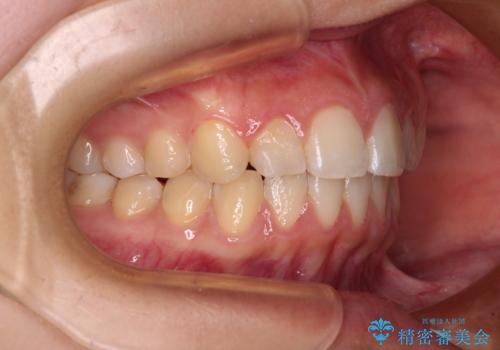

- 前歯の叢生を気にして来院された患者様です。

奥歯の咬み合わせを見ると、上顎が下顎に対して相対的に前方にあり、上下の前歯が接触していない状態でした。

咬み合わせを改善するためには、上顎臼歯を後方に移動させた咬み合わせにする必要があります。

インビザライン単体で改善することも可能ですが、咬合力が強く、単位で達成する可能性が低いと考えられたため、カリエール・ディスタライザーという補助装置を併用して、より確実性を上げることとしました。

奥歯の咬み合わせを改善しながら、並行してインビザラインで歯列を整えることとしました。

カリエールディスタライザーを併用したことで、確実かつ短期間で治療を終えることができました。